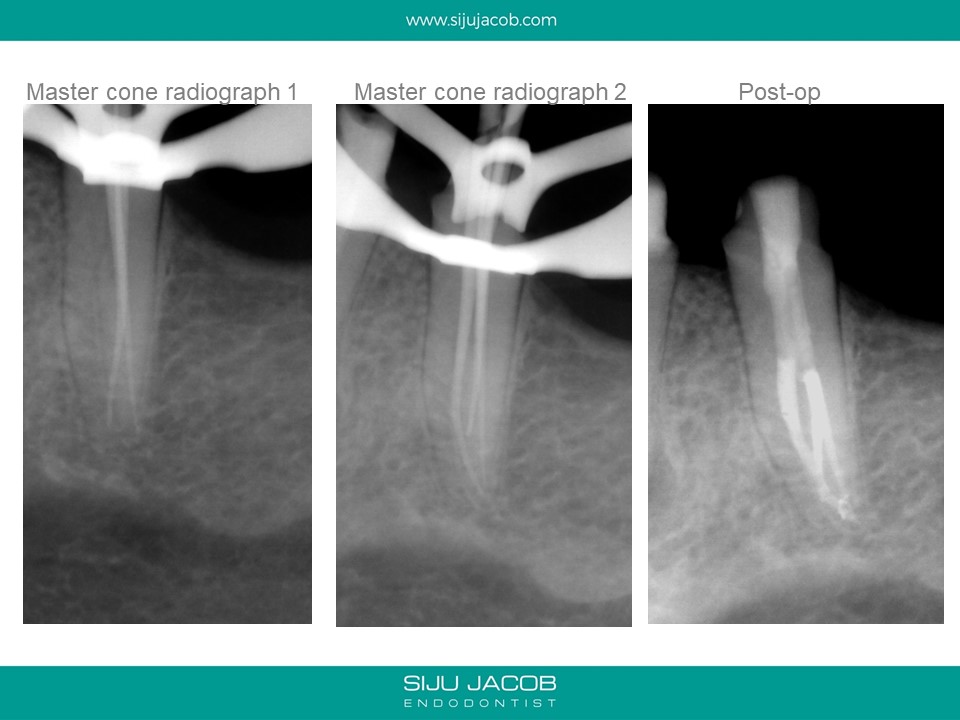

This was referred by a clinician who started the case thinking it was a regular premolar. Looking at the radiograph that the referral e-mailed me, I was expecting a Two-canalled premolar. The master-cone radiograph showed the lack of centricity of the two canals i had discovered. I went back in and found the third canal.